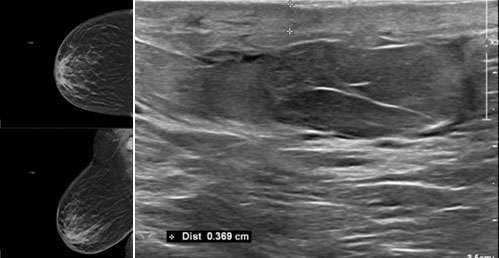

Often, the diagnosis of inflammatory causes of breast skin changes can be made on clinical grounds. When imaging is performed, mammographic and ultrasound findings are nonspecific and similar to the findings listed above for infection of the breast (Figure 1). The role of imaging in these cases is to evaluate for or exclude malignancy.

WU: Skin Change Figure 1

Figure 1. Left image demonstrates CC and MLO mammogram views, with corresponding ultrasound on the right image, of the right breast in a 64-year-old female with lymphoma and chemotherapy via a right Port-a-cath. Mammogram and ultrasound images show diffuse skin thickening and breast edema. Per patient, the onset of skin changes and pain (without erythema) started 3 weeks after a right Port-a-Cath placement. A skin biopsy was negative. The skin thickening and breast edema gradually resolved. Findings were thought to be related to dermatitis or vascular congestion (although no DVTs of upper extremities identified).